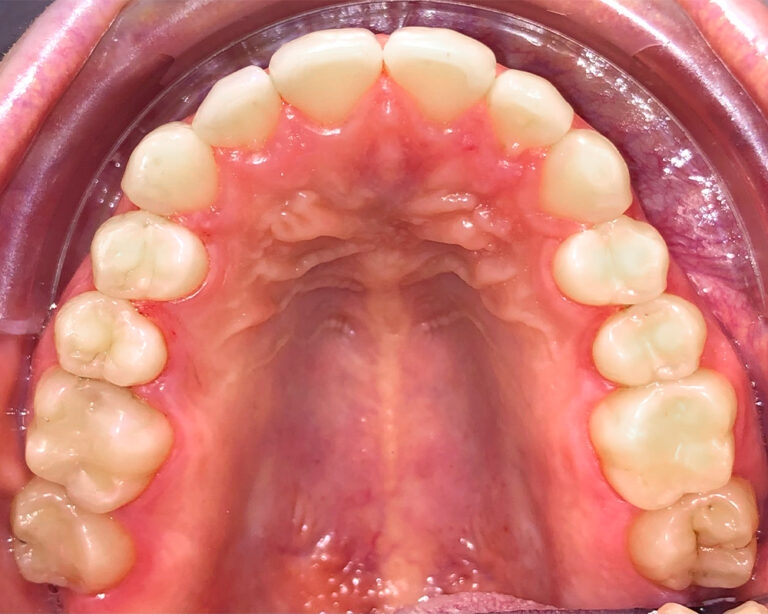

Кейс 11

Акинфиева Анна Владимировна

Количество кап ВЧ 12

Количество кап НЧ 16

ДО

ПОСЛЕ